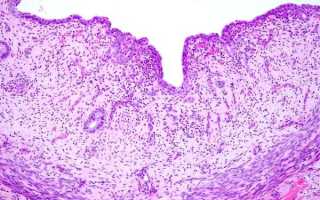

- Ультразвуковое исследование (УЗИ);